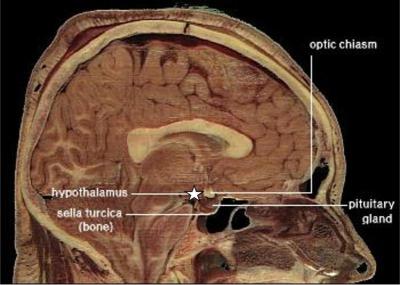

眠くなるのは脳神経の一部がホルモン(メラトニン)を分泌し、血液で体中に巡回し「休憩時間」だと告げる--下画像参照